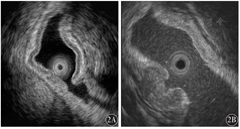

15例GML患者在超声内镜下可见胃壁1~3层的层次结构欠清,呈低回声改变,4、5层结构完整(图2)。

超声内镜在淋巴瘤浸润深度和淋巴结侵袭的判断方面相对精确,可为疾病治疗方案的制订提供必要的信息,并且可以与早期和进展期胃癌进一步鉴别。超声表现大多为低回声,但也有少部分患者是高回声。本研究中GML在高频超声内镜下具有典型的图像改变,可见胃壁1~3层的层次结构欠清,呈低回声改变。高频超声内镜对于GML的辅助诊断有重要意义[6]。同时可在超声内镜引导下进行针对性活组织检查,必要时可采用内镜下黏膜切除术(EMR)或内镜黏膜下剥离术(ESD)等方法帮助确诊。在随访中对于GML与弥漫大B细胞淋巴瘤的转变,高频超声内镜可以有效捕捉信息,指导诊疗及预测预后。因此,合理有效地将放大内镜与超声内镜结合,对于GML的诊断及随访有重要临床意义。但本研究因病例数较少,结论需要扩大病例数、延长随访时间进一步证实。